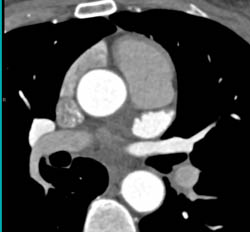

Normal Aortic Root